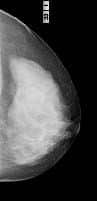

MamaTécnicas de Exploración Radiológica Imágenes mamográficas 8 agosto, 2012 Tidito Clasificacion de una mama normalCasi enteramente compuesta por tejido adiposo (Grasa).Con componente fibroglandular dispersoHeterogéneamente diensaExtremadamente densaProyecciones Cráneo Caudales Proyecciones Oblicuas